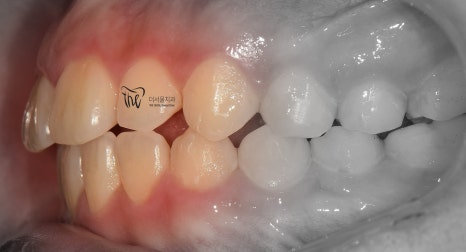

그리고, 정면 및 측면에서 본 모습으로는

살짝 개방교합(Open bite)의 형태를 보여줍니다.

그러면서, 치아들 간의 공간이 조금씩

떨어져 있는 것을 볼 수 있습니다.

마치, 치간이개와 같은 느낌을 받을 수 있으며

앞니들이 앞쪽으로 많이 뻐드러져 있는 형태를

띄고 있습니다.

이럴 경우에는, 무턱 의 증세가 더 뚜렷하게

나타날 수 밖에 없는 상황이 됩니다.